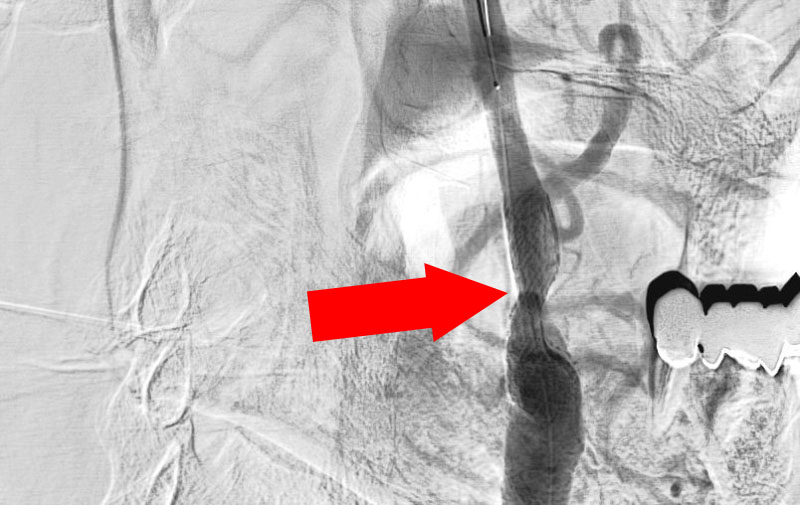

'21年12月

右頚部内頚動脈閉塞症

60代

院内外来

No.1160 手術前

No.1160 手術中

No.1160 手術後